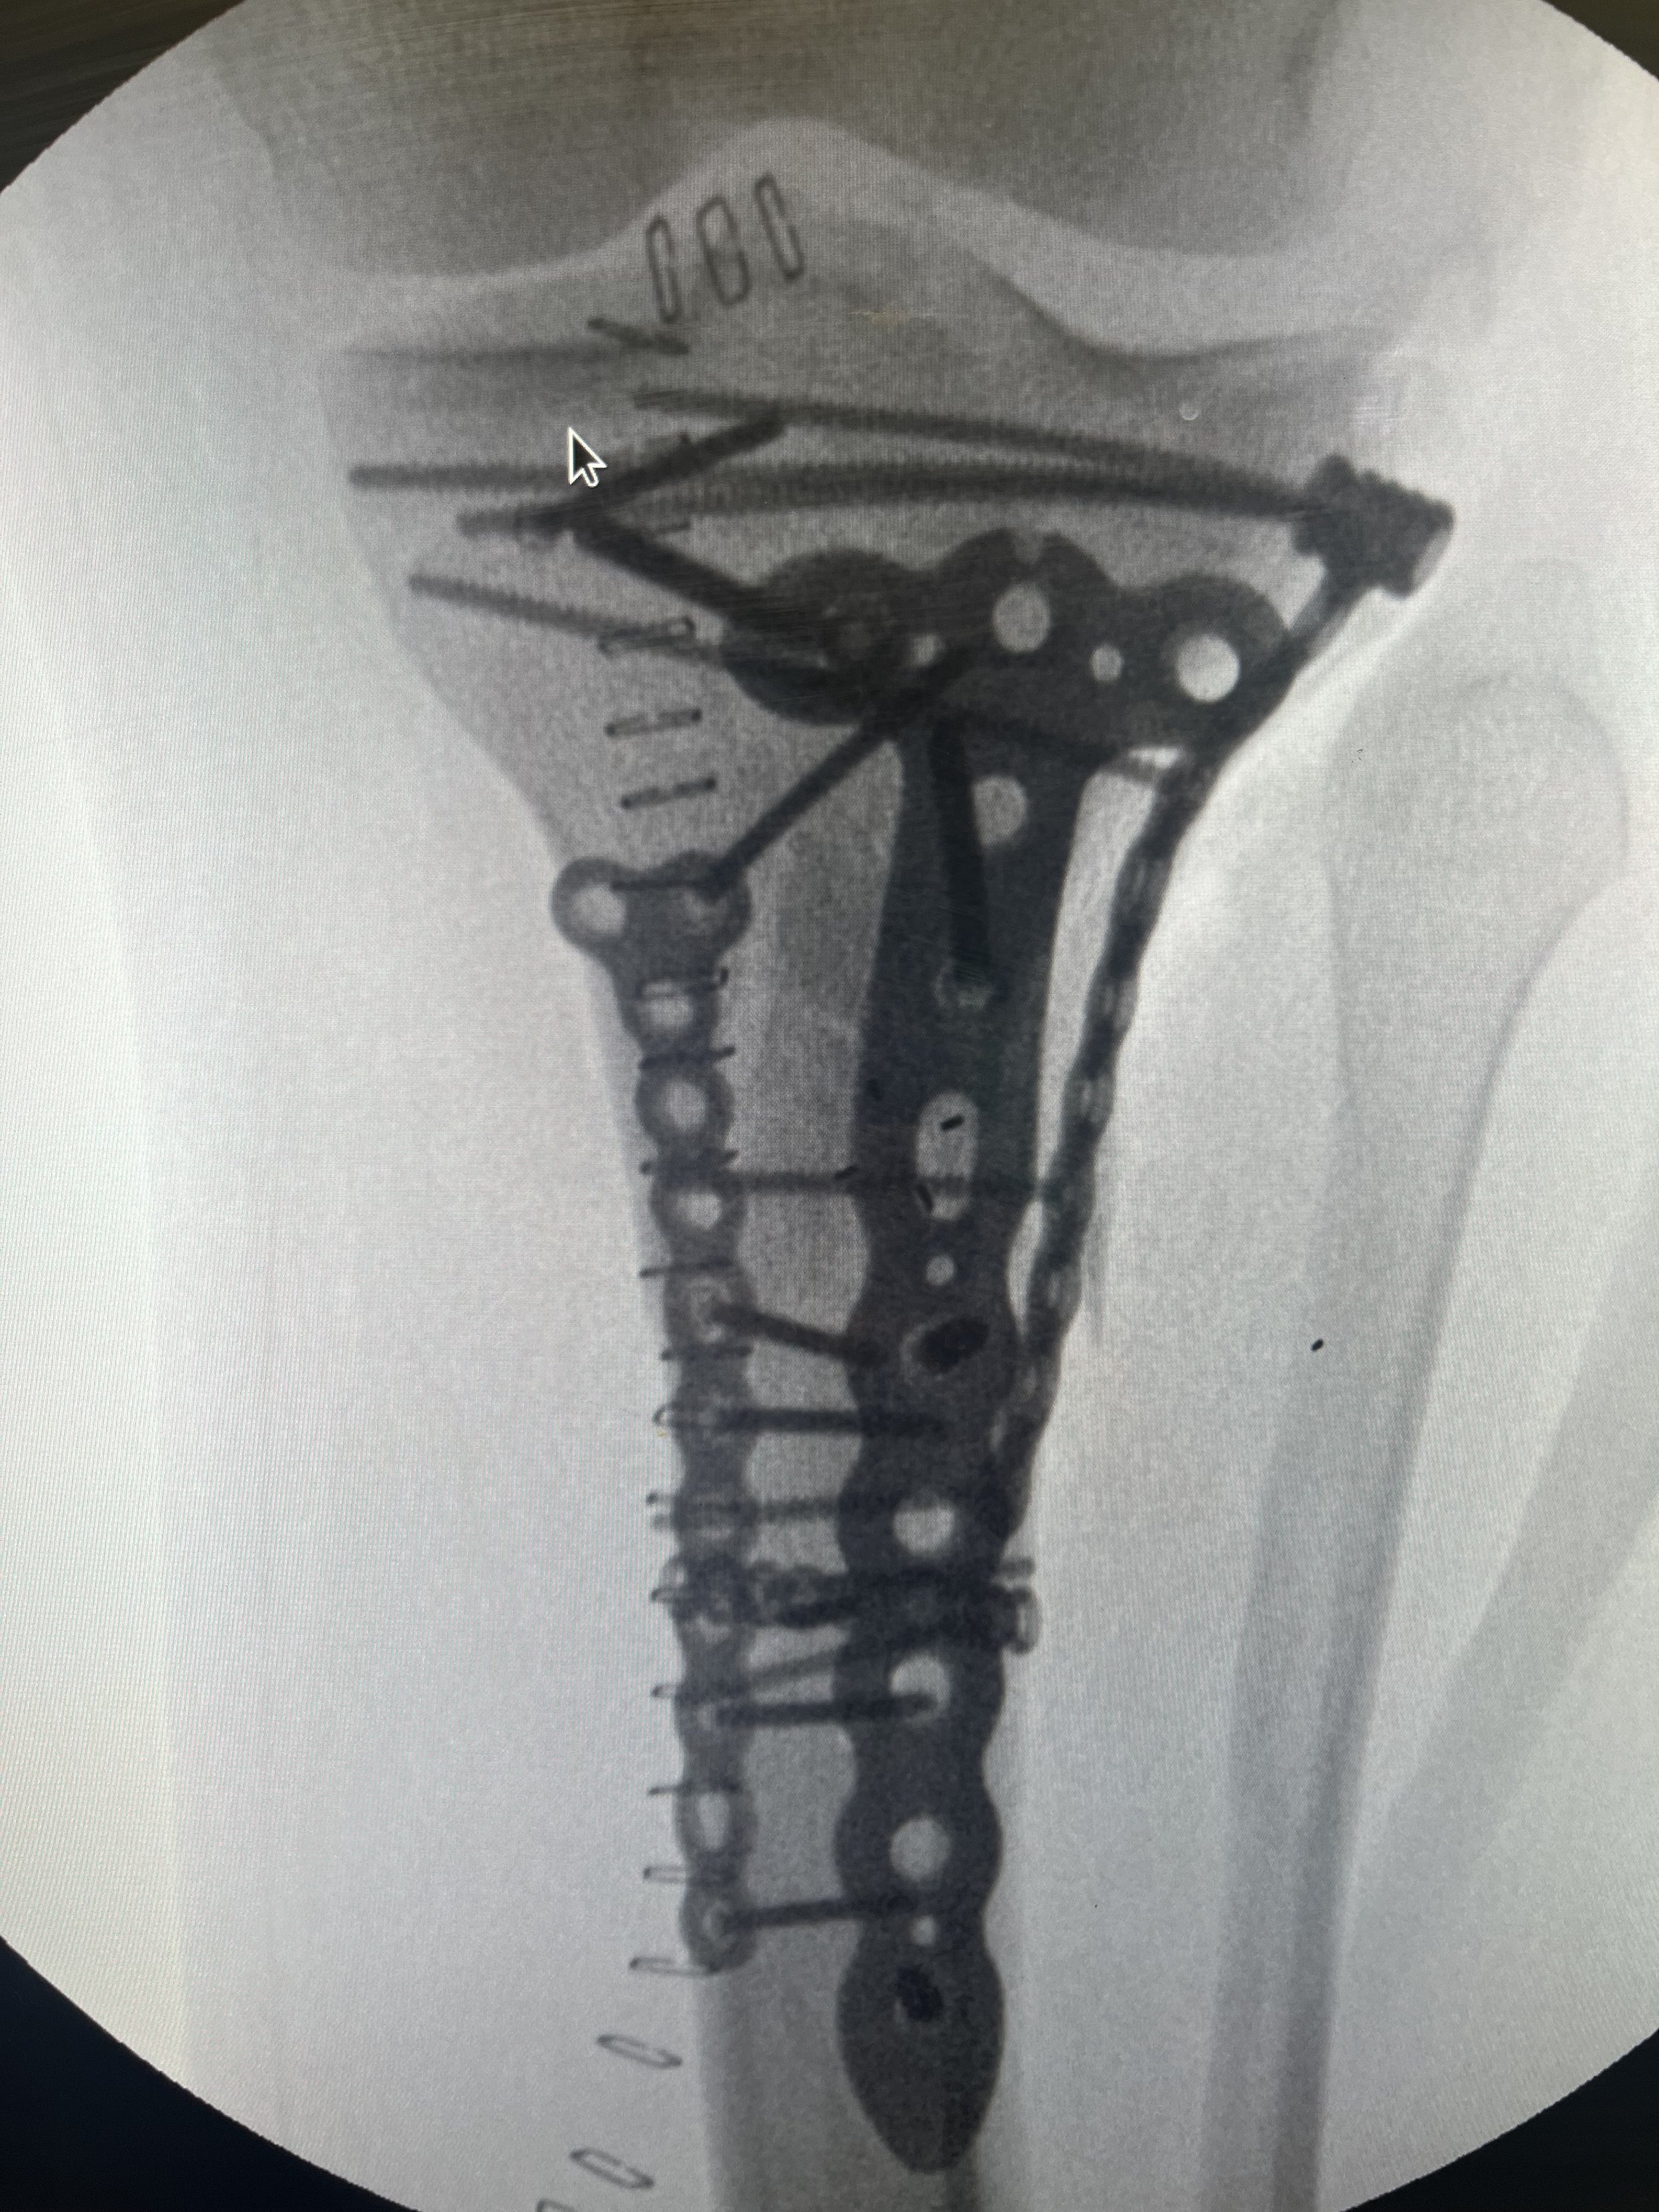

Fracture that did not heal

Fractures that fail to heal (non-unions) or heal improperly (malunions) can cause pain and limit mobility. I specialize in advanced techniques to restore proper alignment and healing.

Revision surgery for failed fracture fixation

If a previous surgery didn’t achieve the desired result, I offer second opinions and surgical solutions to help you recover and regain function.